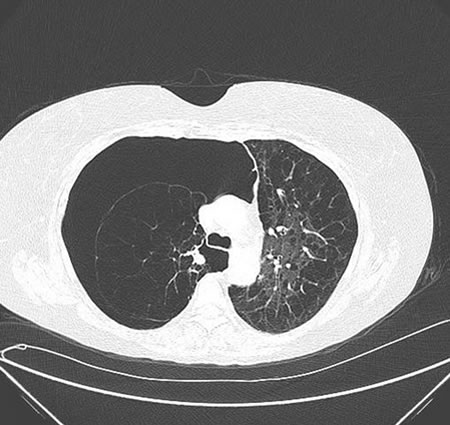

High levels of suspicion are necessary for prompt diagnosis. Chest x-ray or chest computed tomography (CT) confirms the diagnosis. [Figure caption and citation for the preceding image starts]: Chest CT: severe COPD changes with right pneumothoraxFrom the collection of Manoochehr Abadian Sharifabad, MD [Citation ends].